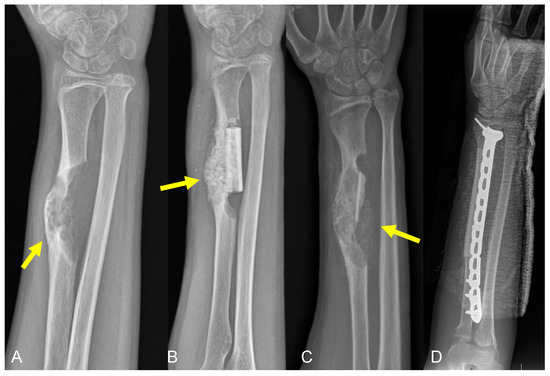

2.2. Type 2 Failures—Loosening and Nonunion

2.2.2. Graft–Host Nonunion

2.3.2. Structural Failure of Allografts